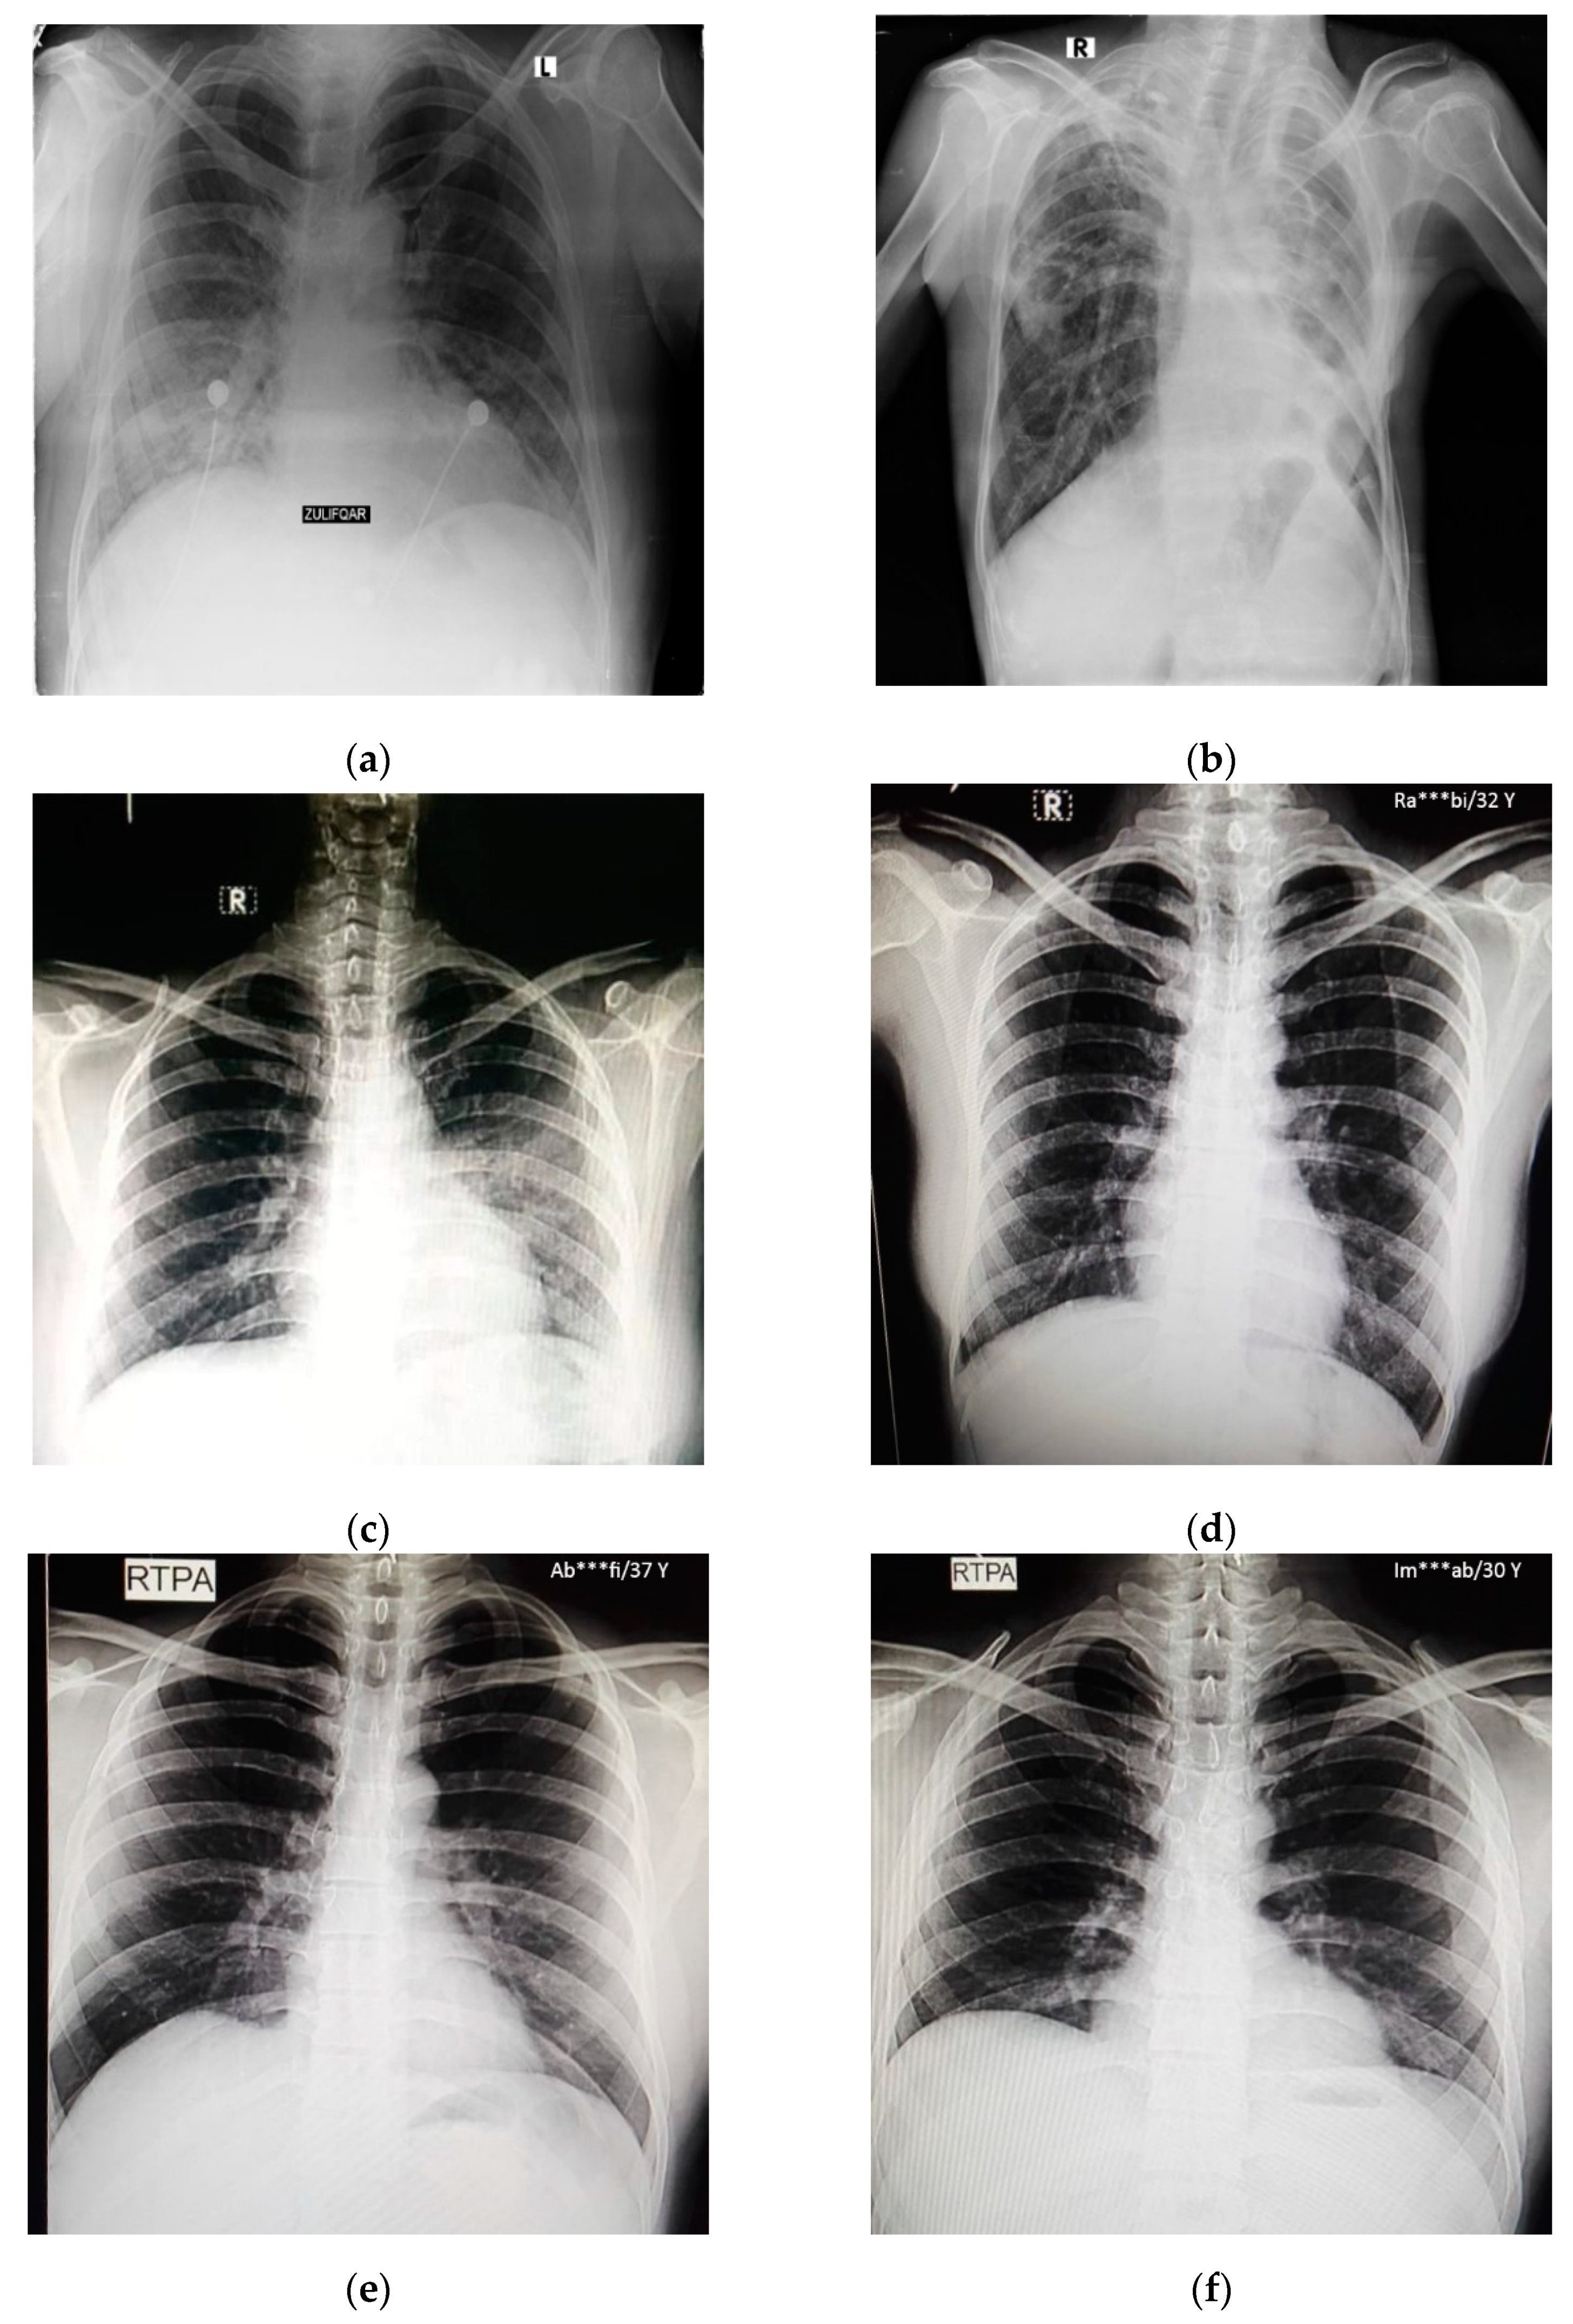

In this study, pulmonary (chest) X-ray images were used for the diagnosis of COVID-19. The dataset was categorized into two main classes, i.e., COVID-19 and normal. A total of 7232 images (3616 COVID-19 + 3616 normal) were accessed from the ‘COVID-19 Radiography Database (available at Kaggle, https://www.kaggle.com/tawsifurrahman/covid19-radiography-database, accessed on 4 May 2021) [30]. From the total images, 70% (5062 images) were used for training + validation, and the remaining 30% (2170 images) were used for testing purposes. The training + validation dataset of 5062 images was further split into a 70:30 ratio, i.e., 3544 (70%) images for training purposes and 1518 (30%) images for validation purposes. The details of the data splitting are given in Table 1. In addition to the dataset accessed via Kaggle, another locally collected dataset of 450 images (COVID-19 + normal) was also used for testing and prediction purposes. This indigenous data of chest X-ray images of Pakistani COVID-19 positive and normal patients have been collected from a local hospital. The samples of normal and COVID-19 X-ray images assessed via the Kaggle database are shown in Figure 1, whereas the samples of the locally collected images are given in Figure 2.

Figure 2.

Samples of local Pakistani verified dataset used for the testing of trained models: (a–c) COVID-19 chest X-rays; (d–f) normal chest X-rays.